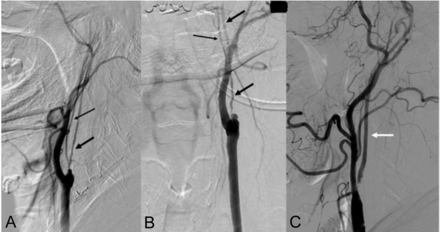

The angiographic findings in the patients with near-occlusion are listed in Table 1. Angiographic examples of near-occlusions with and without collapse are demonstrated in Fig 1. There was no significant difference between the near-occlusion with collapse and near-occlusion without collapse groups based on patient characteristics (Table 2). The near-occlusions were symptomatic in 41 patients (70.7%, including 23 patients with stroke, 16 patients with TIA, and 2 patients with acute ICA occlusion after the diagnosis of near-occlusion) and asymptomatic in 17 patients (29.3%). Two patients (1 with collapse and 1 without collapse) were treated emergently for acute ICA occlusion, which developed as the patient was waiting for a CAS procedure after the elective cerebral DSA. Otherwise, CAS was performed electively.

A and B, Near-occlusion with collapse. Cervical angiograms in lateral and anteroposterior projections, respectively. Thick black arrows indicate the string sign in near-occlusion with collapse. Thin black arrows indicate ascending pharyngeal artery. The ascending pharyngeal artery should not be confused with near-occlusion with collapse, especially in the setting of total ICA occlusion. C, Near-occlusion without collapse. Lateral cervical angiogram shows tight stenosis of ICA origin and diameter reduction in distal cervical ICA (white arrow) compared with the ipsilateral external carotid artery.